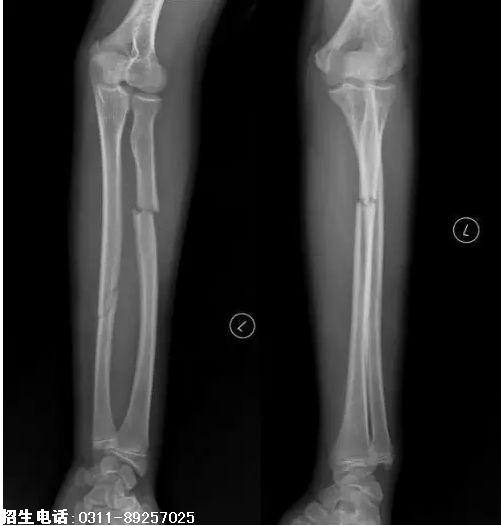

6、题干:男,15岁。左上肢外伤20分钟。结合X线片,此诊断为

答案:A

解析:由图可看出是左前臂骨折,左前臂的尺骨和桡骨均有骨折,可诊断该患者为左尺桡骨双骨折。(A对)